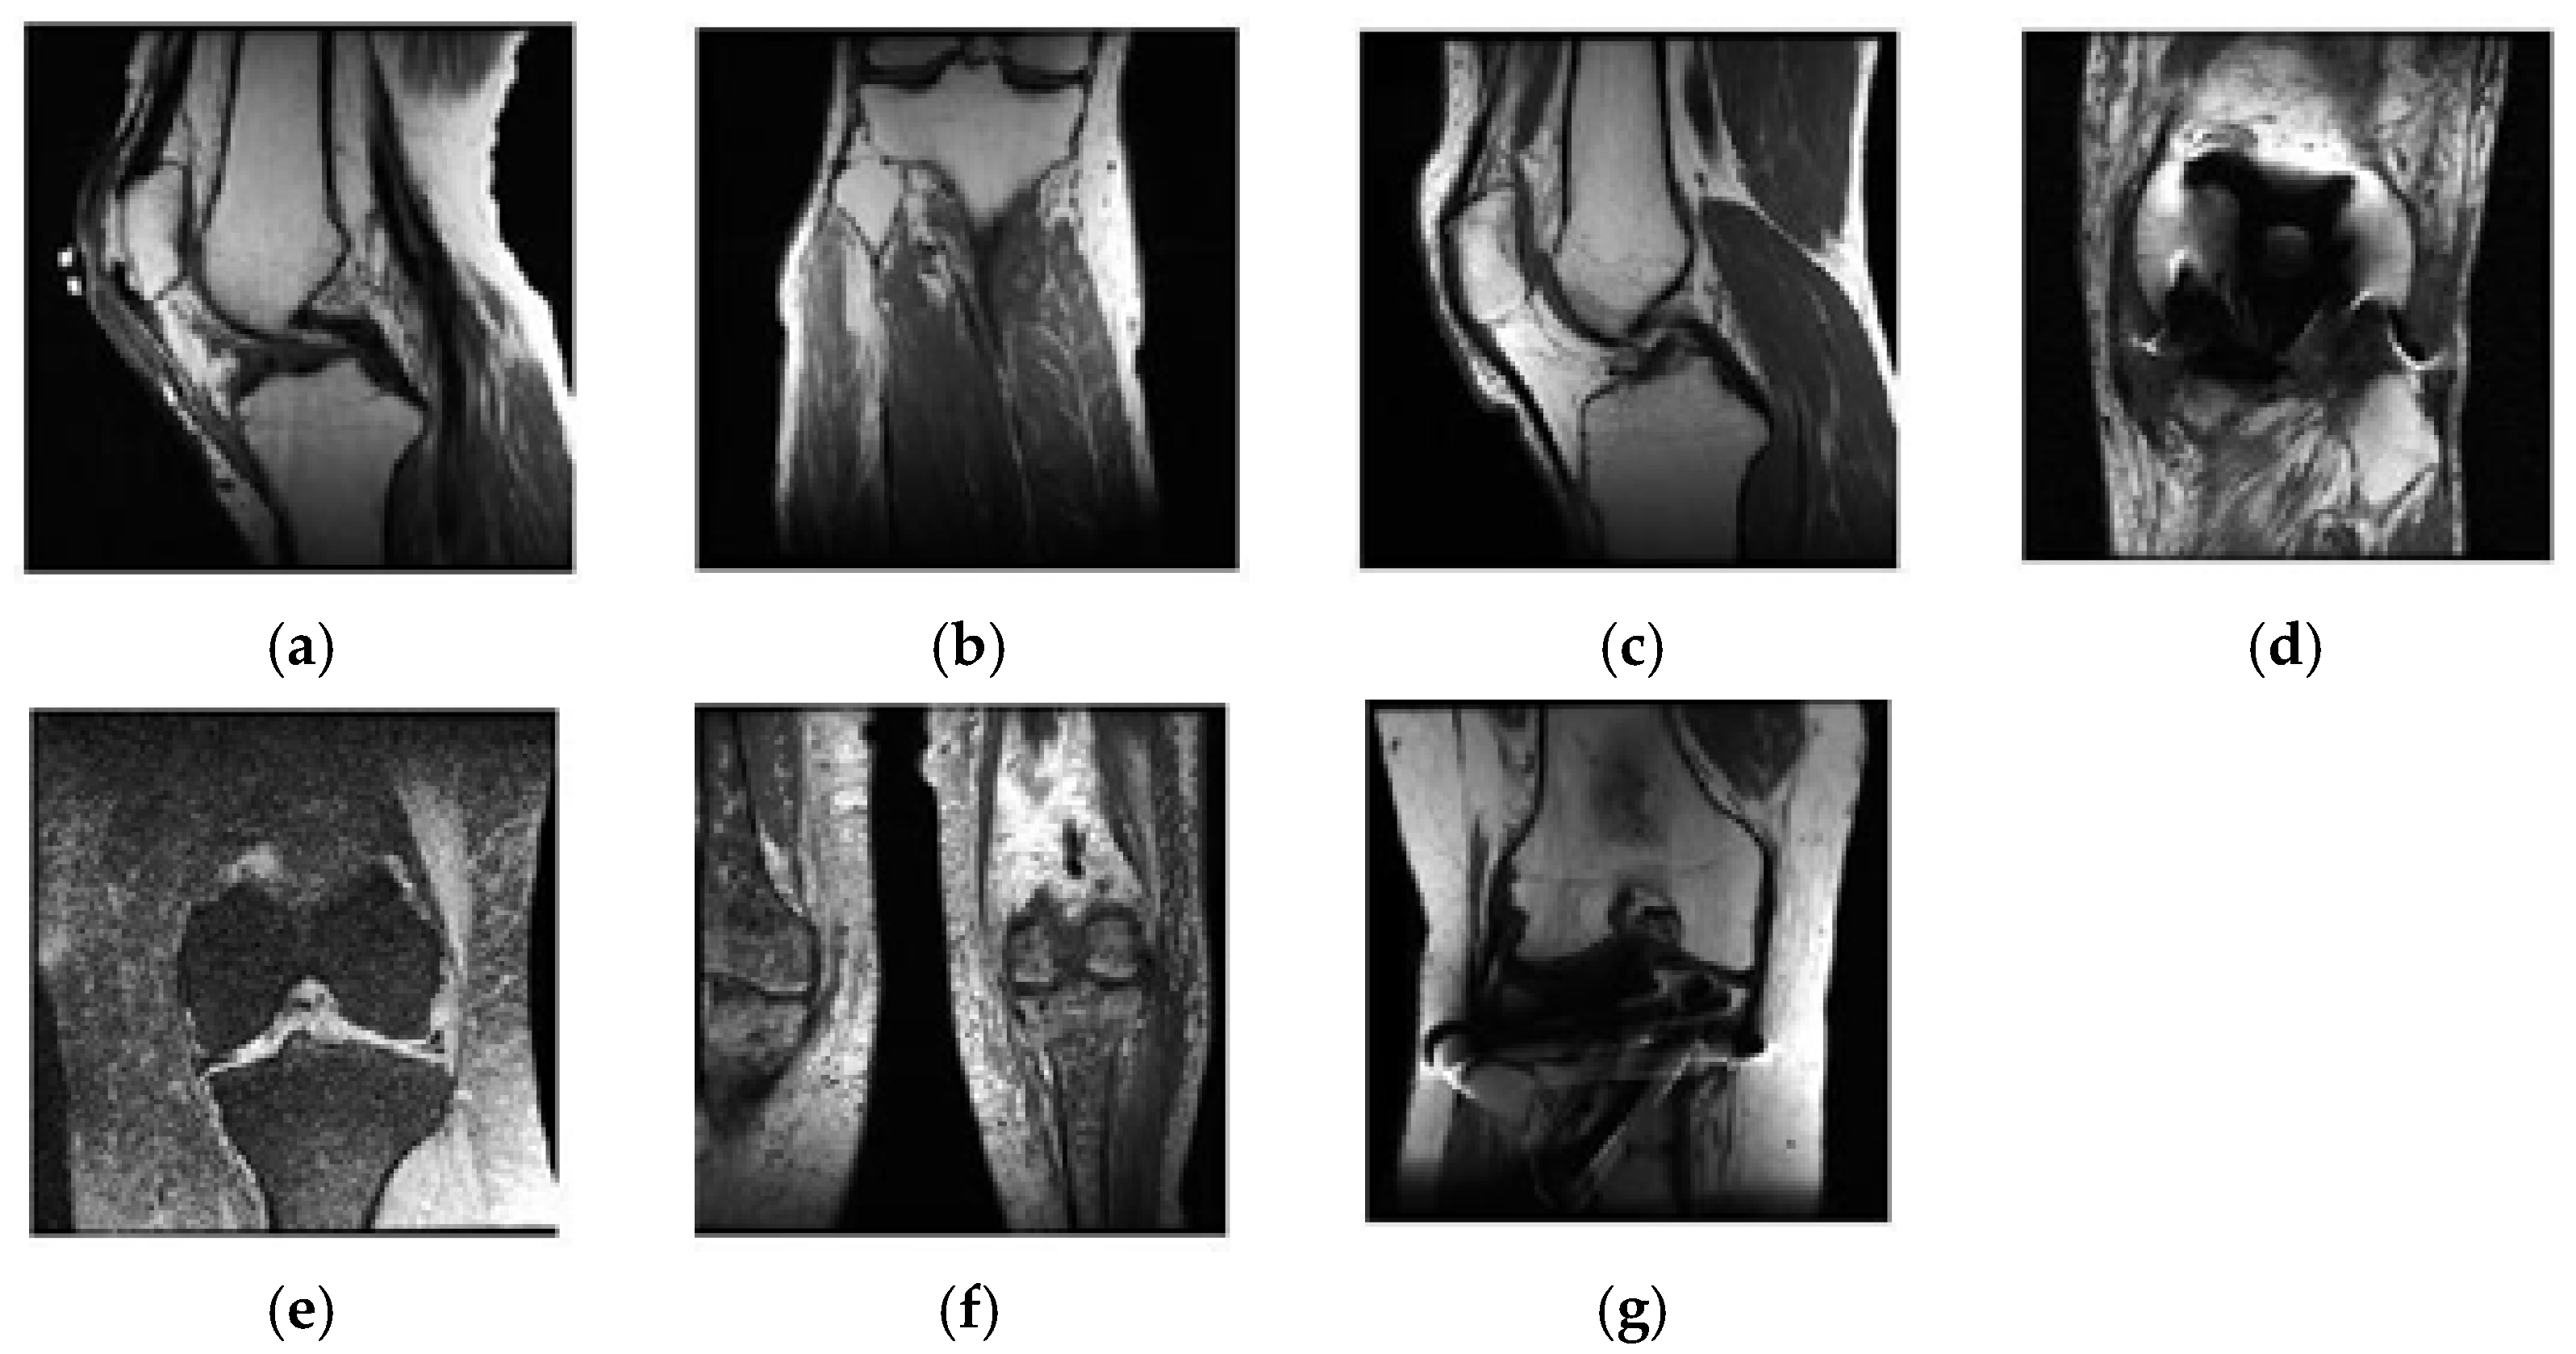

2.3.1. Classification of Sagittal Images and Results

2.3.2. Classification of Coronal Images and Results

2.3.3. Classification of Axial Images and Results

2.4.1. Selecting Relevant Areas on the Sagittal Axis

2.4.2. Selecting Relevant Regions on the Coronal Axis

2.4.3. Selecting Relevant Regions on the Axial Axis